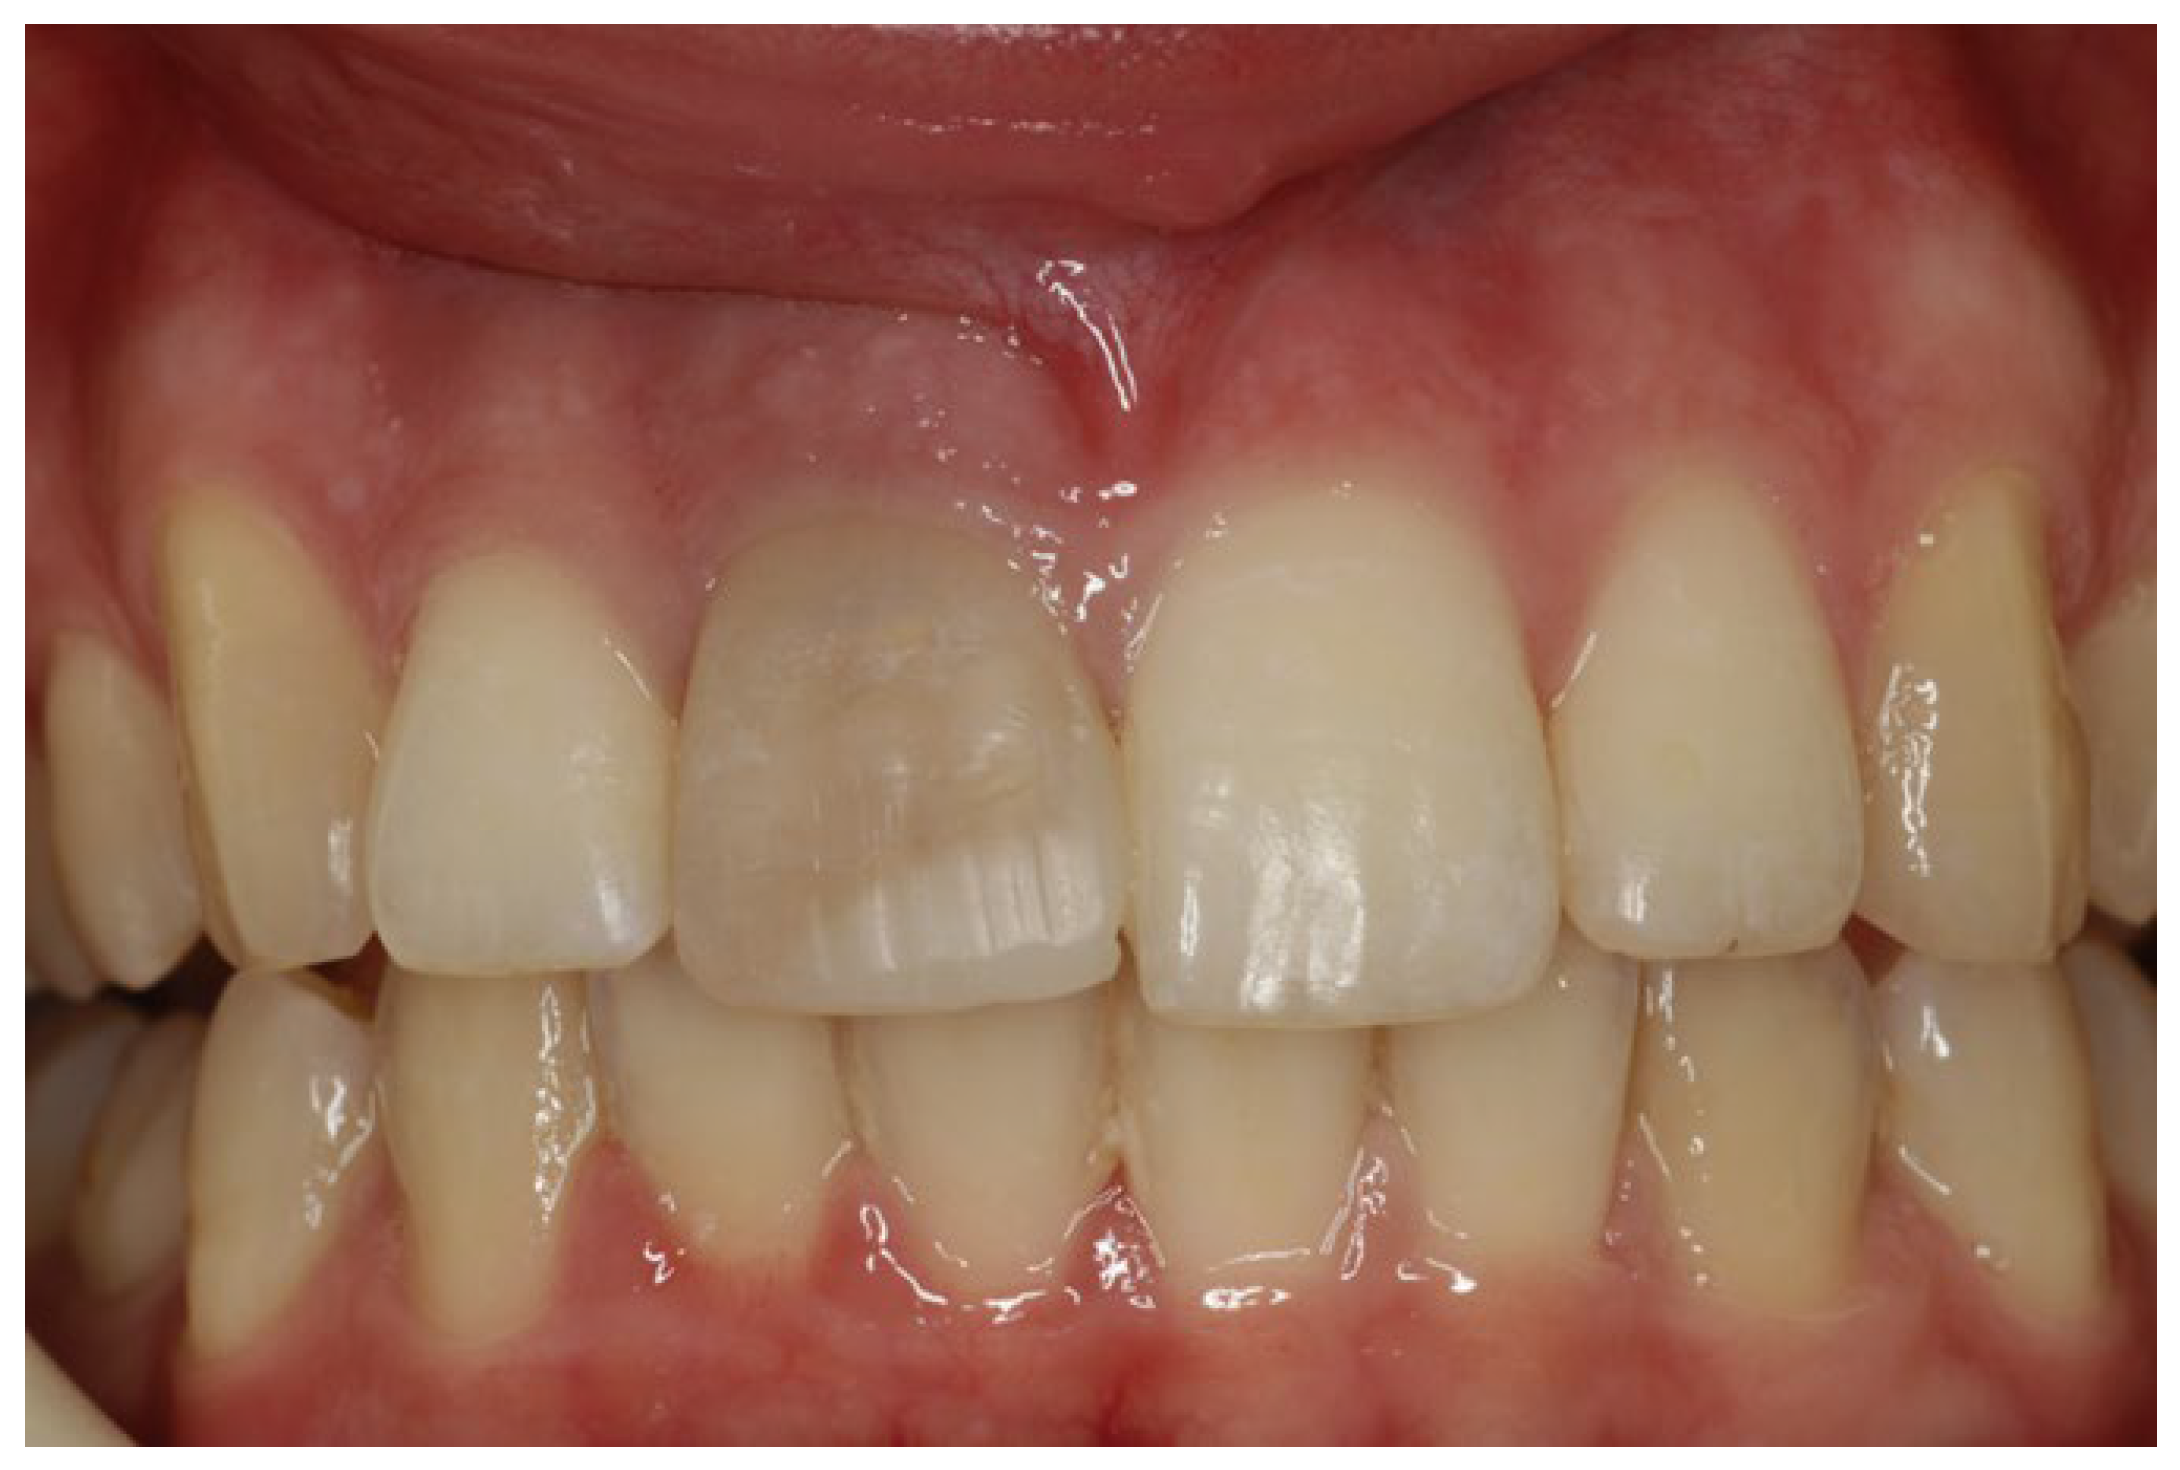

2. Clinical Case